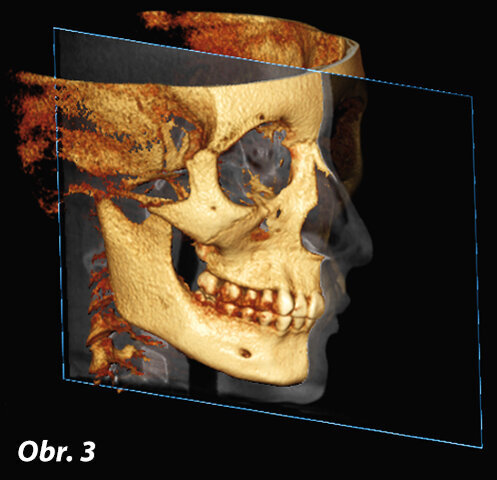

Sagitální rovina (obr. 3, 4)

Sagitální rovina rozděluje lebku na dvě symetrické části. Umožňuje vyšetření dvou segmentů: pravého a levého.